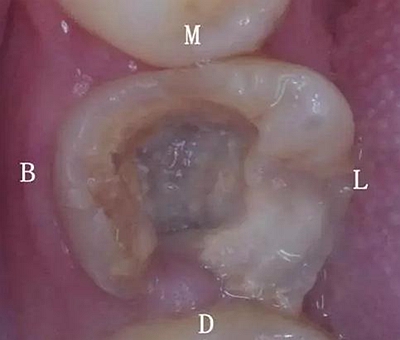

初診時口內(nèi)照片:

初診時X光片:根分歧炎癥懷疑有底穿,和患者交待病情和費用后開始治療。